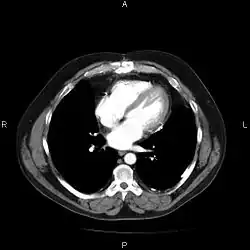

System archiwizacji obrazu i komunikacji (ang. picture archiving and communication system, w skrócie PACS) – technologia przetwarzania obrazów medycznych, która zapewnia ekonomiczny sposób składowania oraz wygodny dostęp do obrazów z różnych źródeł. Elektroniczne obrazy medyczne i raporty są przesyłane cyfrowo poprzez PACS – eliminuje to potrzebę ręcznego archiwizowania. Uniwersalnym formatem dla składowania i przesyłania obrazów PACS jest DICOM (Digital Imaging and Communication in Medicine). Inne dane niż obrazy np. zeskanowane dokumenty mogą być przechowane używając standardowych formatów jak PDF.

- urządzenie produkujące cyfrowe zdjęcia medyczne (CT, MRI, Ultrasonograf),